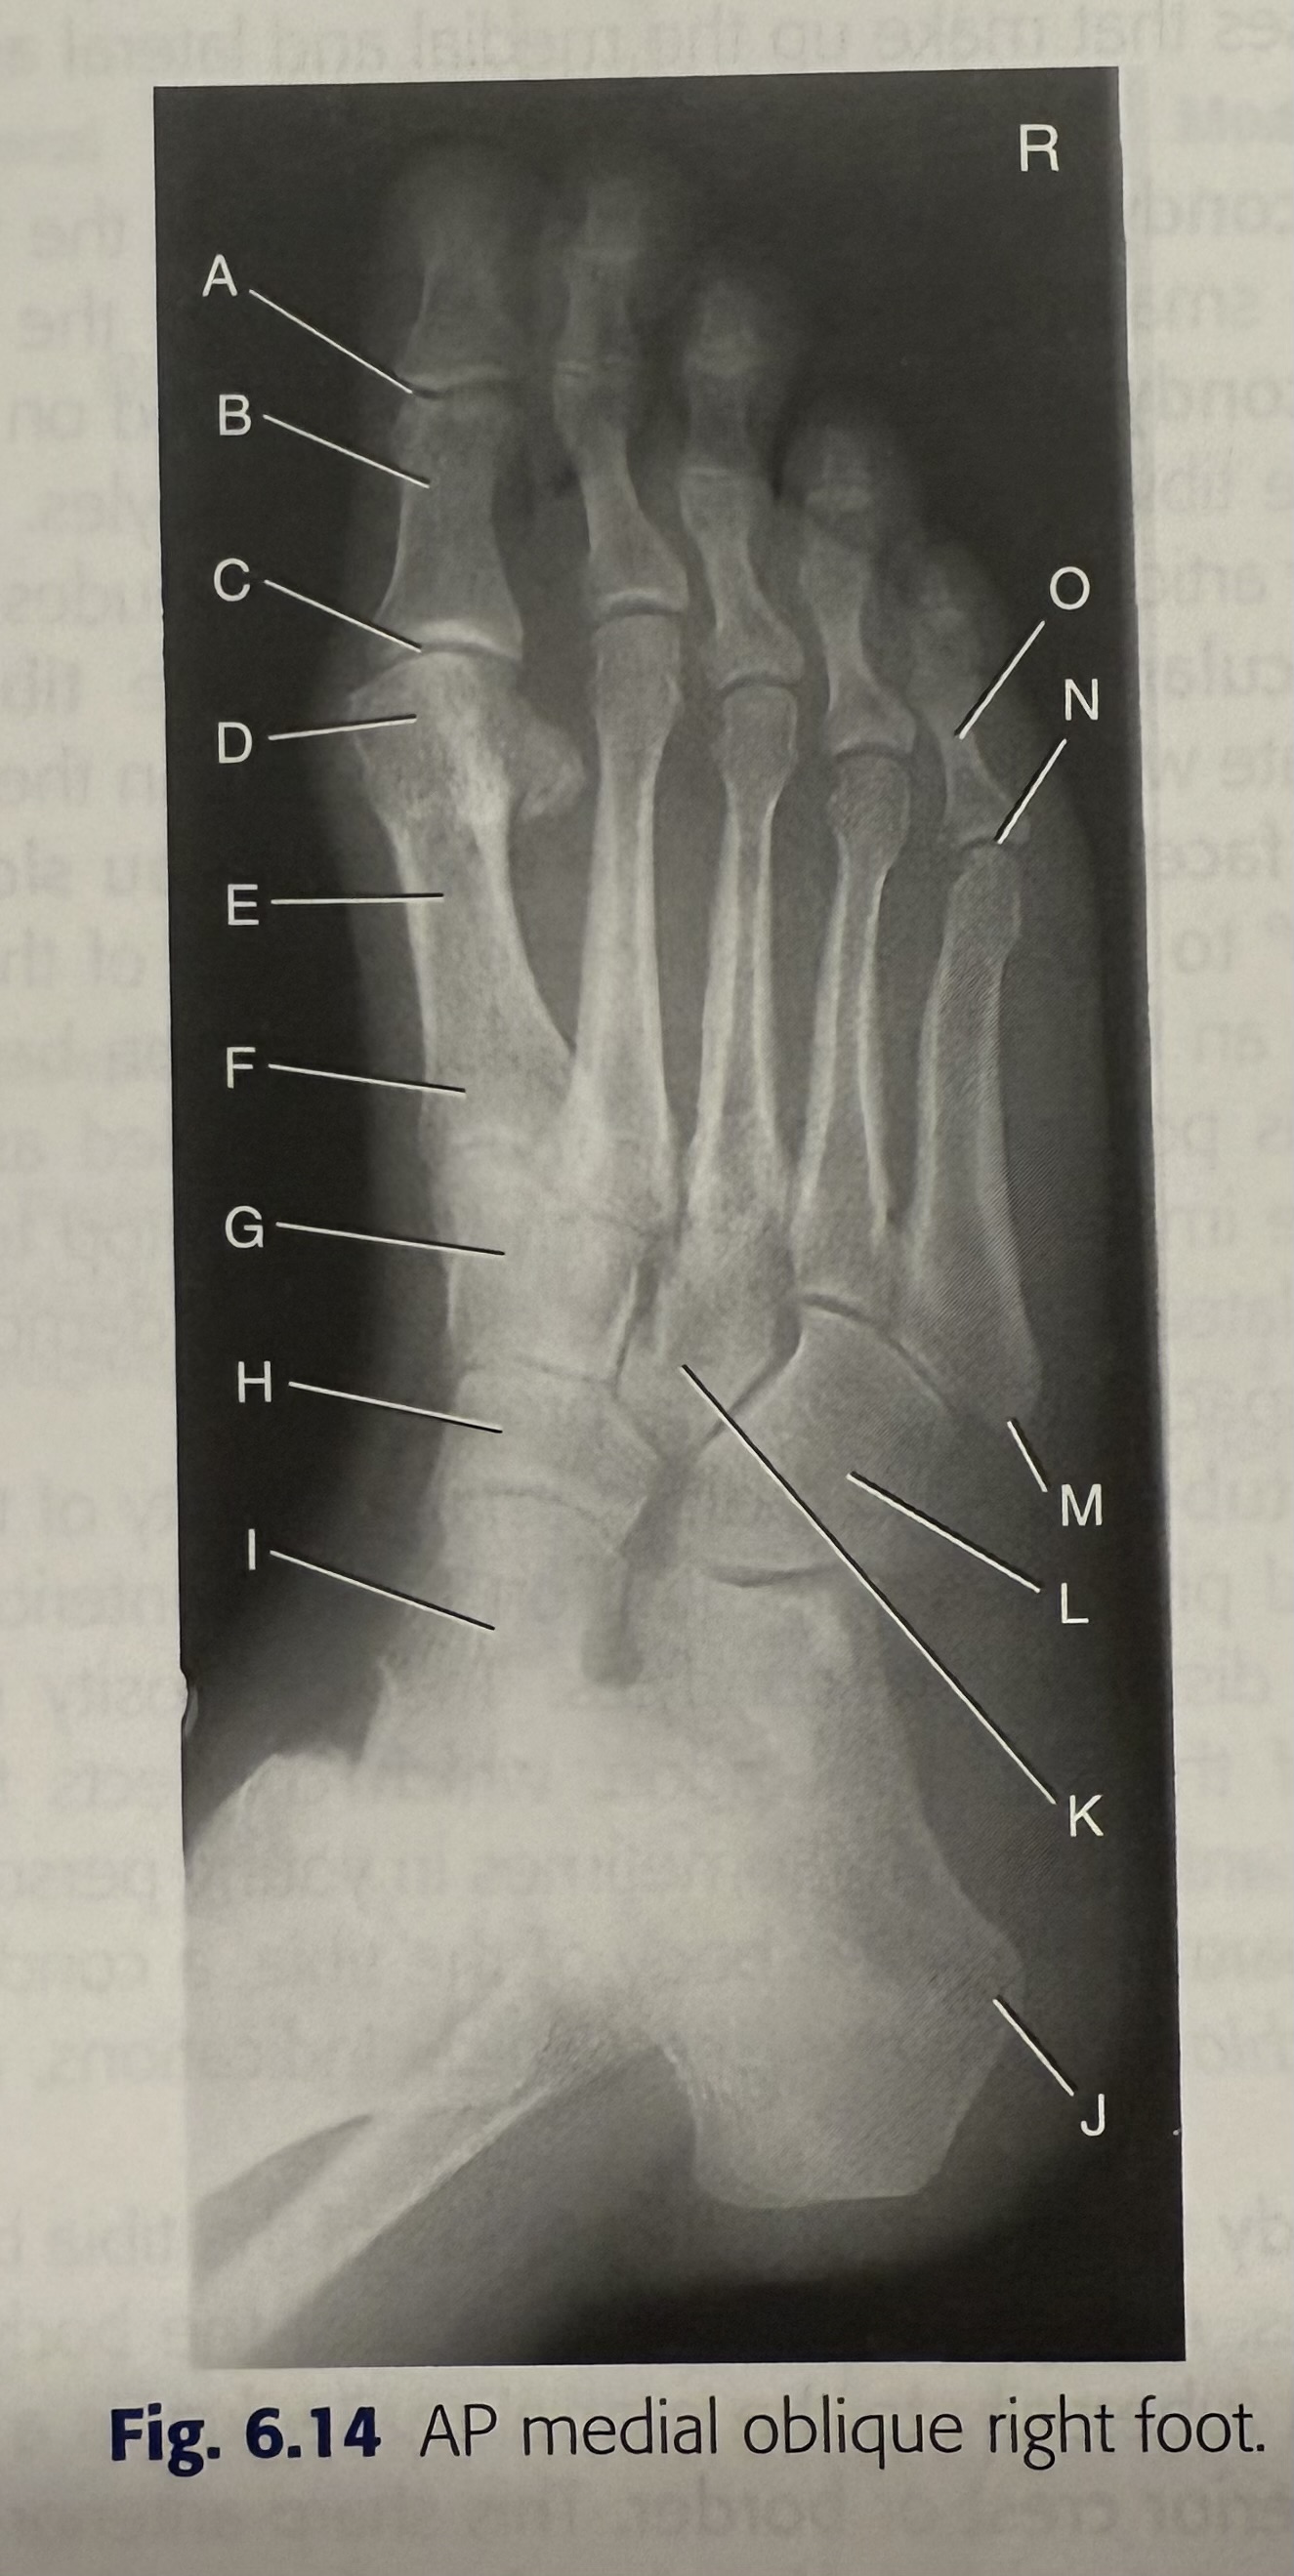

lateral malleolus

9

New cards

<p>D</p>

D

mortise

10

<p>E</p>

E

tibia

11